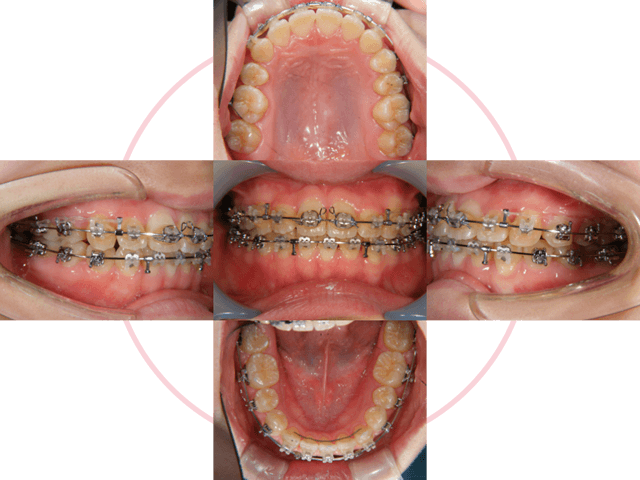

3

動的期間1年半で終了です。

4

ブラケットを外しました。上は着脱式の保定装置、下は前歯の裏側で保定しています。